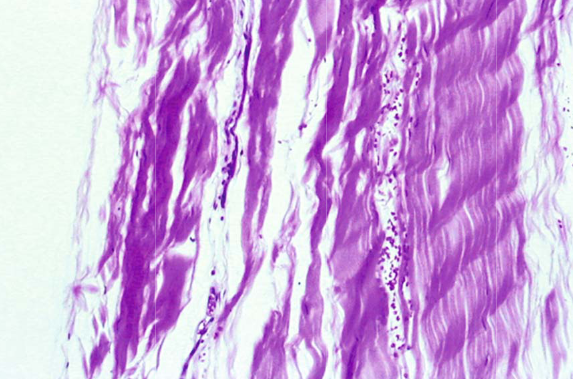

На гистопатологическом уровне наблюдаются изменения в молекулярной структуре сухожилия, часто связанные с расщеплением и дегенерацией коллагена.

на изображении схематично показано тандинопатия сухожилия голнесотопного сустава